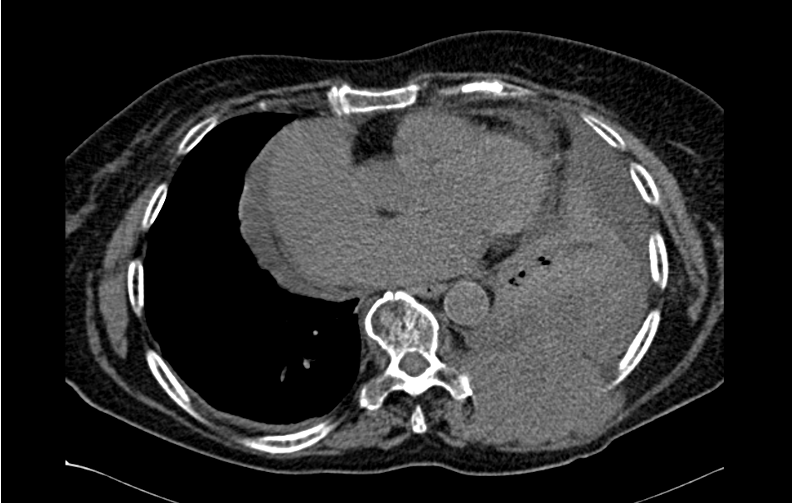

Liver Abscess Secondary to Duodenal Perforation After Fishbone Ingestion: A Case Report

Fernanda Pombo Rodriguez, Matheus Antônio Chiconelli Zangari, Rodrigo Piltcher-da-Silva, Vivian Lais Sasaki, Doroty Eva Garcia Felisberto, Júlio Cezar Uili Coelho, Eduardo José Brommelstroet Ramos, Micheli Fortunato